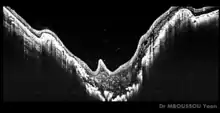

On fundoscopic examination, there are three principal findings comprising the anomaly:[5]

- an enlarged, funnel-shaped excavation in optic disc

Morning glory syndrom OCT - an annulus or ring of chorioretinal pigmentary changes surrounding the optic disc excavation

- a central glial tuft overlying the optic disc